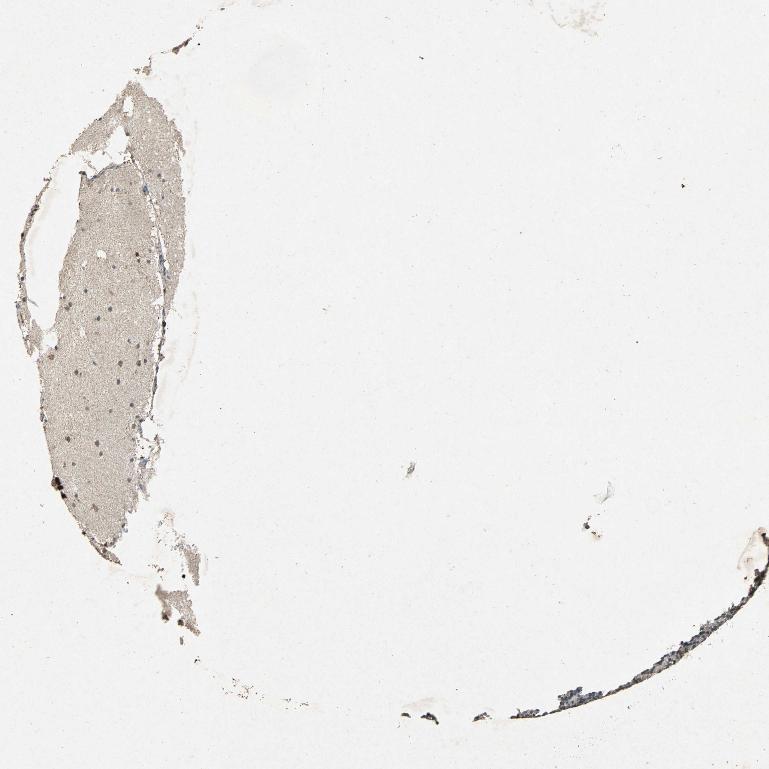

CEREBELLUM - Antibody stainingi

Antibody staining in the annotated cell types in the current human tissue is reported as not detected, low, medium, or high, based on conventional immunohistochemistry profiling in selected tissues. This score is based on the combination of the staining intensity and fraction of stained cells.

Each image is clickable and will lead to virtual microscopy that enables deeper exploration of all samples and also displays staining intensity scores, fraction scores and subcellular localization as well as patient and tissue information for each sample.

Antibody HPA030711Antibody CAB006269

Purkinje cells HighHigh

Cells in granular layer Not detectedMedium

Cells in molecular layer Not detectedHigh